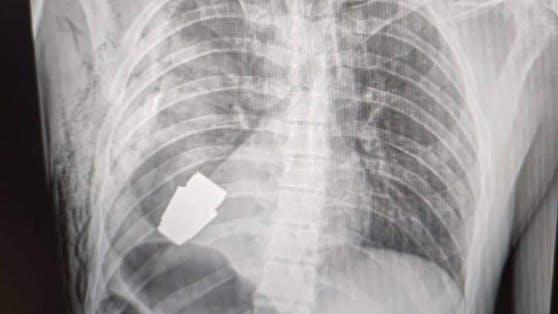

Die Geschichte medizinischer Ausnahmeoperationen ist um ein Kapitel reicher: Ein erfahrener Militärchirurg brachte es fertig, einem verwundeten ukrainischen Soldaten eine Granate aus dem Brustkorb zu holen, die jederzeit hätte explodieren können.

Andriy Verba, einer der erfahrensten Militärärzte des Landes, musste bei der OP anders vorgehen als sonst üblich. Die Methode der Elektrokoagulation, bei der Wechselstrom durch den Körper des Patienten geleitet wird, um Blutungen zu kontrollieren, durfte er wegen der Explosionsgefahr nicht anwenden. Zudem waren bei der heiklen Entfernung des Geschosses zwei Spezialisten der Armee anwesend, um die Bewegungen des Arztes zu überwachen: Die Granate hätte jeden Moment hochgehen können.

Beim Geschoss soll es sich um eine sogenannte VOG-Granate gehandelt haben, die aus tragbaren russischen Granatwerfern verschossen werden. Meist sind die Projektile mit Streugeschossen gefüllt, die bei der Detonation alles um sie herum zerfetzen.